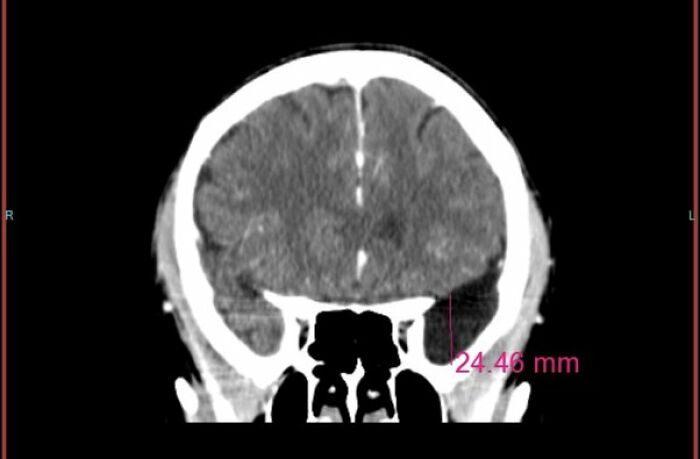

Mój tata skarżył się na silne bóle głowy, myślał, że potrzebuje nowej recepty na okulary. Po jednym ataku, który go powalił, zabraliśmy go na SOR. Tomografia ujawniła guz mózgu. Operowali go dwa dni później po zmniejszeniu obrzęku; dano mu przewidywanie 3–6 miesięcy życia, ale przeżył 6,5 roku i spędził ten czas z rodziną, doświadczając niewielkich skutków ubocznych poza wrażliwością na hałas i tłumy.

Podczas jedzenia burgera nagle nie byłem w stanie otworzyć ust — myślałem, że to TMJ. Chirurg ust zalecił pilną operację po badaniu, ale zlecił też MRI — i wtedy przekazał mi drugą, przerażającą wiadomość: „Mamy masę w mózgu. Proszę iść do neurologa.” Okazało się, że to duża torbiel zaklinowana w okolicy lewego płata skroniowego. Na razie nie da się jej bezpiecznie usunąć, więc lekarze monitorują wzrost. To doświadczenie wstrząsnęło mną, bo dowiedziałem się o tym tuż przed zabiegiem związanym z żuchwą.